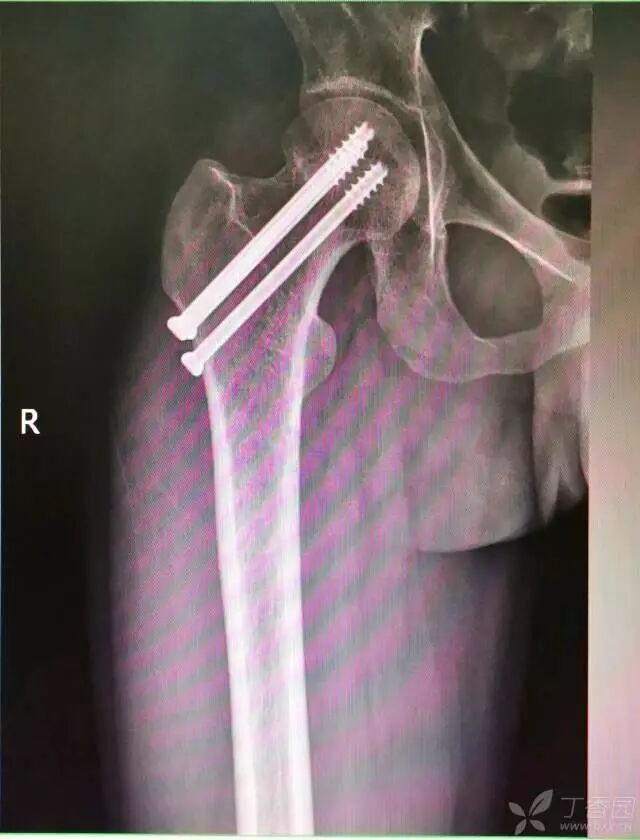

8. 最后测深依次拧入合适长度的螺钉

牵引床怎么用视频详解:如何不使用牵引床做好一台股骨颈骨折?_https://www.jmylbn.com_新闻资讯_第17张

术后复查

术后十个月复查,骨折愈合,正常行走。